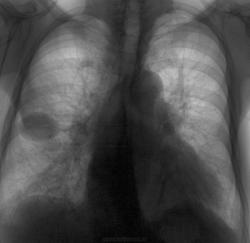

А это не жидкость в междолевой плевре?

Положительная динамика очаговых изменений в верхних отделах обоих легких. Справа, похоже междолевой плеврит. Клиника? Лабораторные данные?

Интересно, как оценить не только это, но и то... что слева... Да и базальные отделы справа в паренхиме неспокойны.